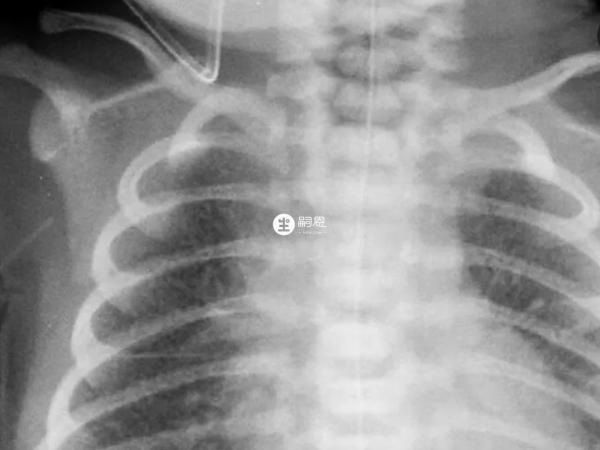

新生兒溼肺的早期症狀就是呼吸急促,60次/分以上,口脣青紫等等,而新生兒吸入性肺炎的早期症狀表現為呼吸困難、青紫,口吐泡沫,肺部有溼羅音等等。新生兒溼肺和肺炎的區別主要就是病因不同、病症表現有差異、治療方法也不同,而且新生兒肺炎還分為吸入性肺炎和感染性肺炎。

- 2. 病症:新生兒溼肺早期症狀表現為呼吸急促、伴有呻吟、口脣青紫等,嚴重為呼吸可達100次/分以上、青紫明顯、缺氧、酸中毒以及黃恆持續時間長。吸入性肺炎早期症狀表現為呼吸困難、青紫,可從口腔中流出液體或泡沫,肺部有溼羅音,一般症狀和體徵持續時間超過72小時;